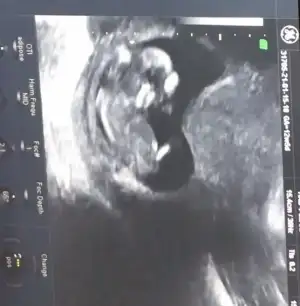

Erkek görünüyorAmin canım hepimizin12 haftalık usg resmi benimde

Bakalım bu hafta gidicem büyük ihtimal söyler heraldeErkek görünüyor